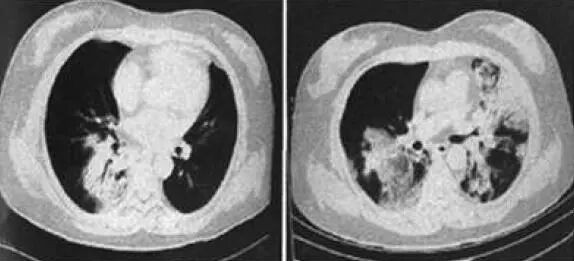

胸部CT,主要表现,还是双肺弥漫性分布的实变影及磨玻璃影。

病灶多,变化快,气难喘,斑片+磨玻璃。

另外一例,先看胸片。

流感:进展快,才能体现我是病毒的疯狂!

再看CT:

同上,似乎流感喜欢跑到胸膜周围搞破坏,但是一般没有胸水!不合并细菌感染,几乎不会引起空洞。